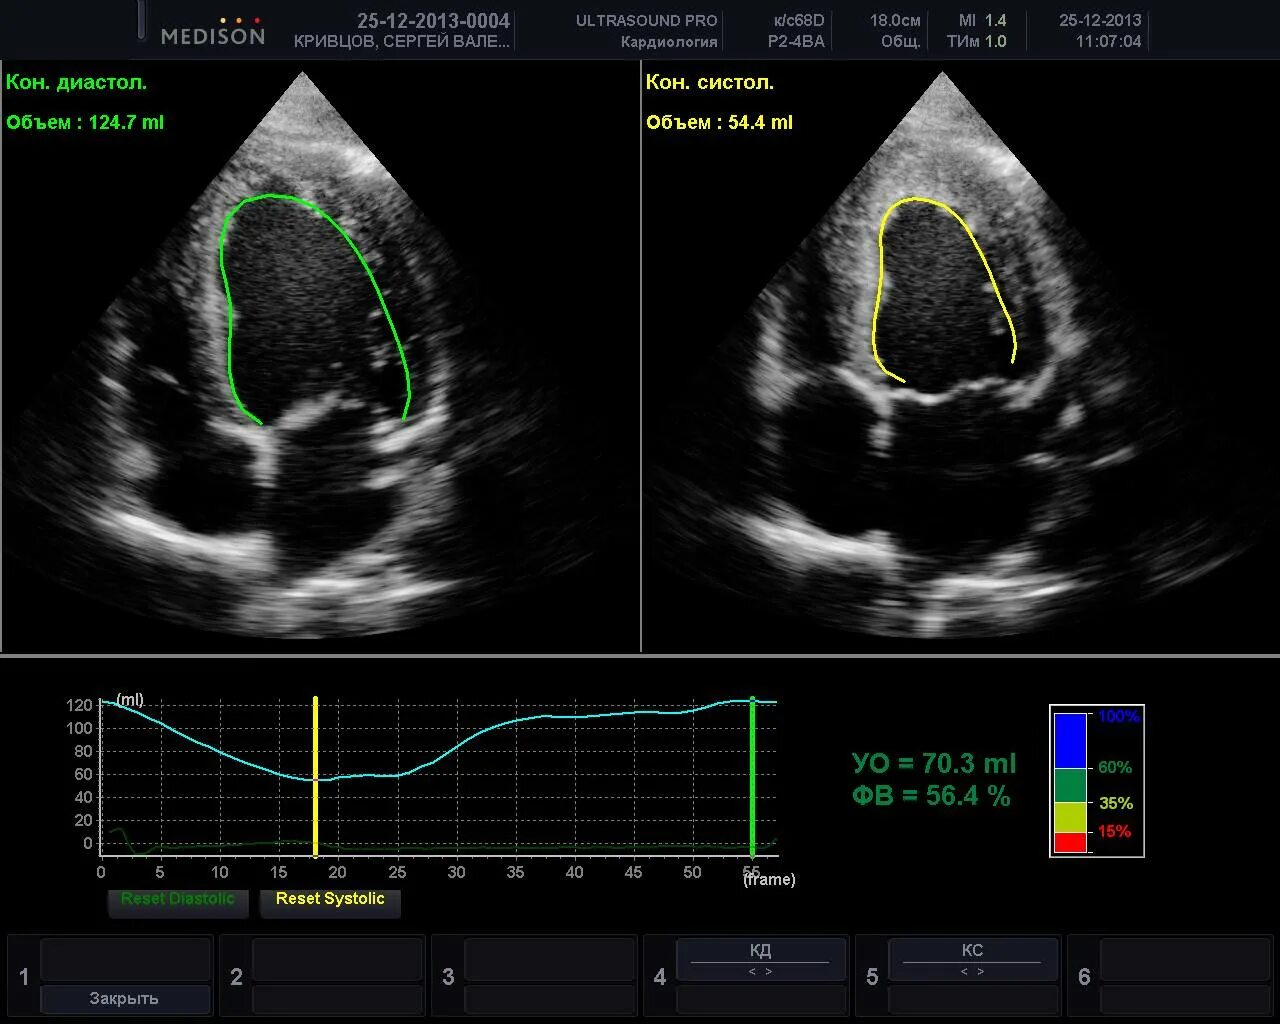

Эхокардиография как делают женщинам